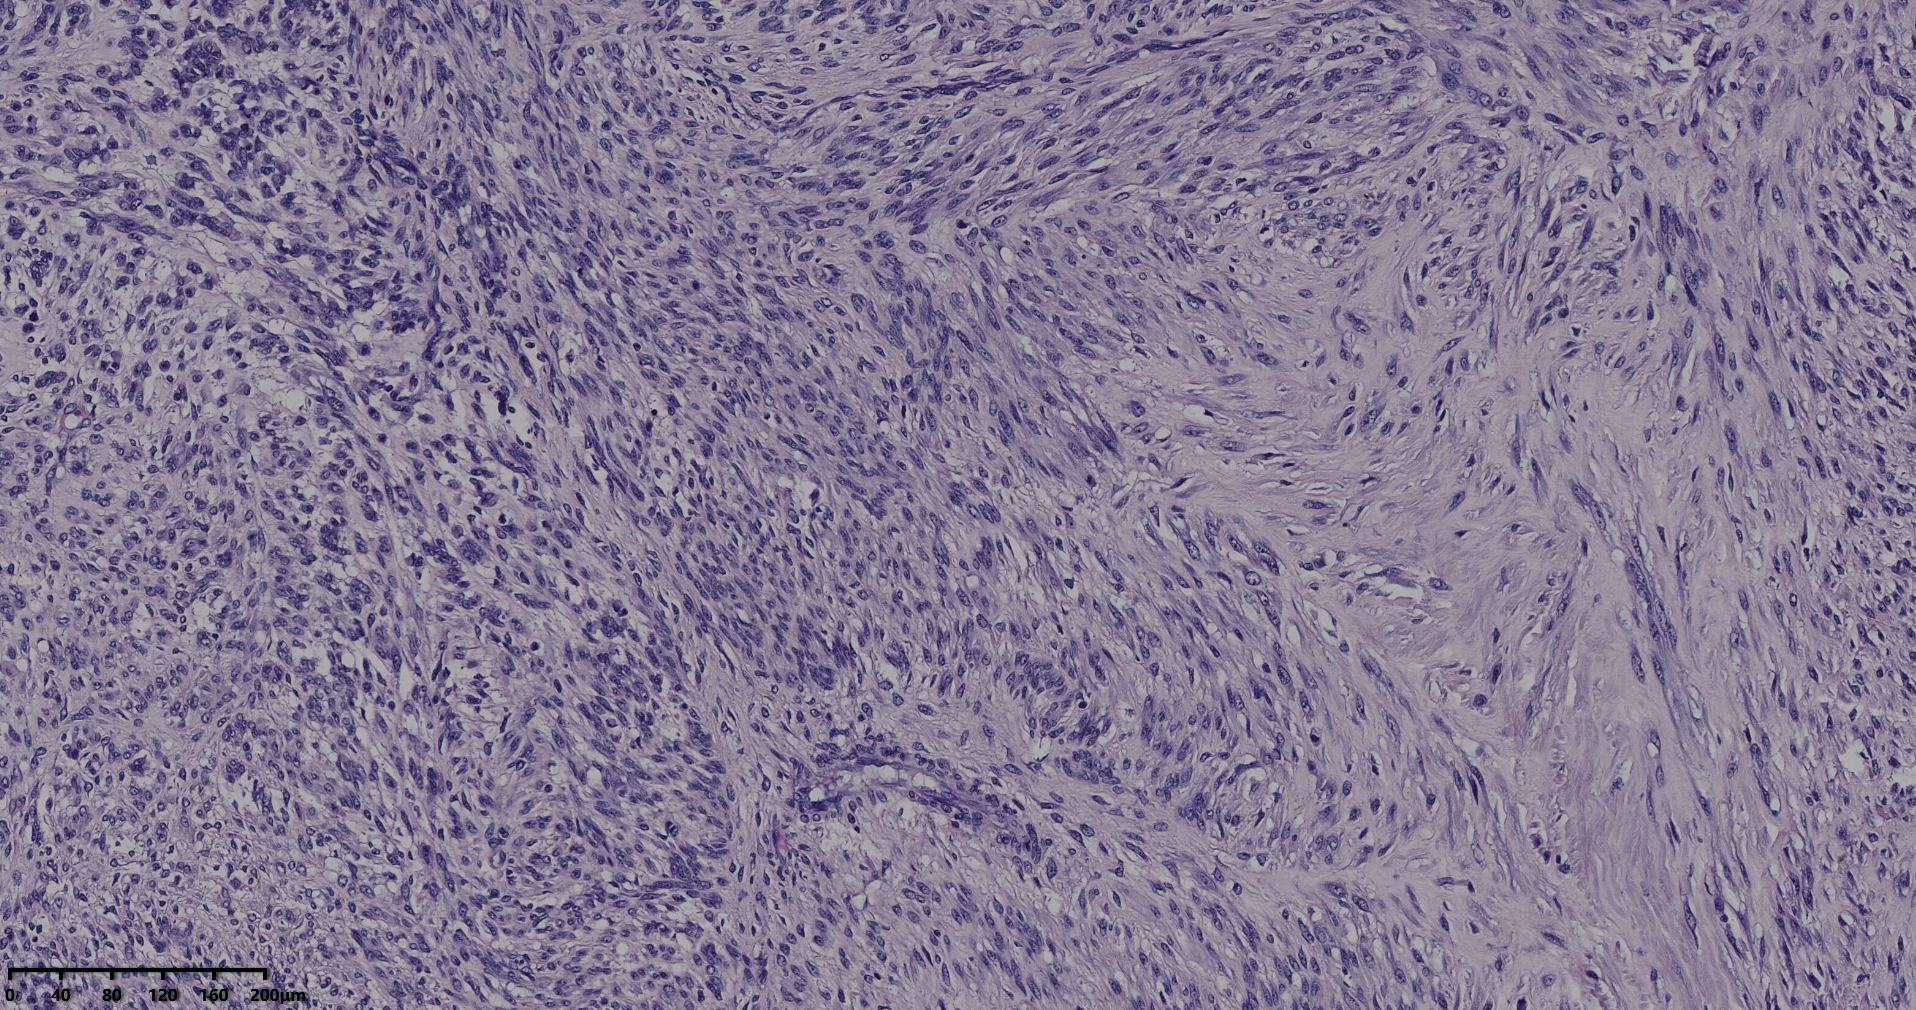

镜下所见小肿物无特殊,大肿物瘤细胞密集,中心区有变性、坏死,瘤细胞核有异型性。大肿物补充取材,发现,部分区域切面灰黄,这个区域,瘤细胞更密集,异型性更显著。肿物边缘有薄层正常平滑肌组织被覆,靠近边缘瘤细胞最密集,局部瘤组织内小血管较丰富。

会诊:考虑平滑肌肉瘤。

北医三院会诊:子宫平滑肌瘤伴红色变性可能性大,建议加做免疫组化及NGS检测进一步明确诊断。